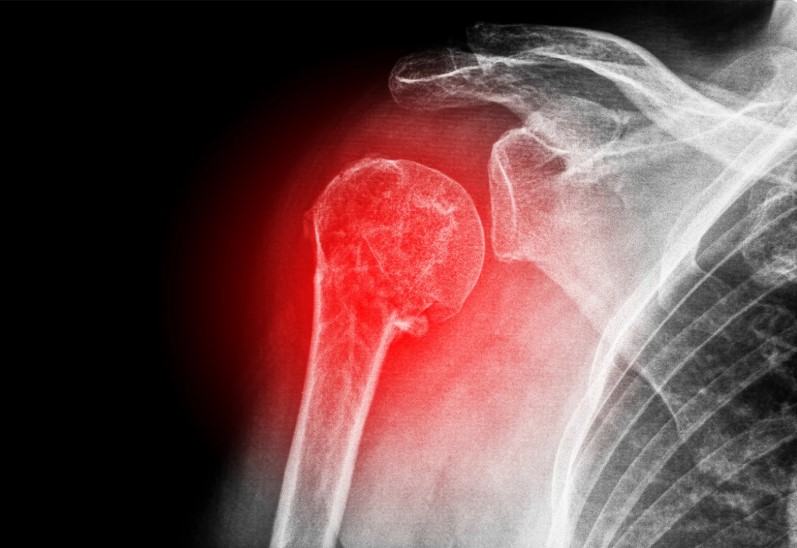

The shoulder works as a complex joint system formed by the clavicle, scapula, and upper arm bone. These structures allow wide movement while supporting strength and stability. Trauma such as falls, road accidents, sports injuries, or weakened bone density may cause breaks across one or more parts of this system. When a fracture occurs, bone fragments may shift away from proper position, creating pain and limiting motion. Shoulder Fracture Surgery Quezon City addresses these issues by restoring alignment and protecting long-term shoulder function.

Not every shoulder fracture needs an operation, yet certain patterns benefit greatly from surgical correction. Clavicle fractures may shorten or overlap, changing shoulder balance. Proximal humerus fractures often disturb the ball-and-socket area, leading to stiffness and weakness if healing occurs without alignment. Scapular fractures usually follow high-impact trauma and can affect shoulder stability. Shoulder Fracture Surgery Quezon City becomes a strong recommendation when bone displacement, joint involvement, or multiple fragments threaten normal recovery.

Persistent pain despite rest and medication often signals a complex fracture. Visible deformity, bruising, or abnormal shoulder shape may appear. Many patients experience difficulty raising or rotating the arm, along with weakness that interferes with self-care or work tasks. Imaging studies showing displaced or unstable fracture patterns frequently guide specialists toward Shoulder Fracture Surgery Quezon City as a safer option for long-term results.